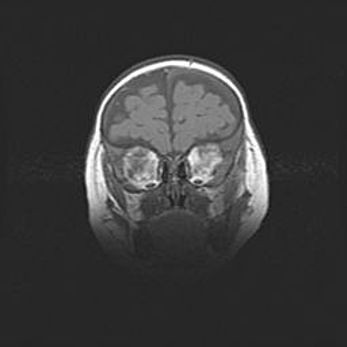

Церебральная ишемия II.

Возраст: 5 дней

Вес: 3400 г

Пол: женский

Окружность головы: 35 см

Срок гестации: 39 недель

Церебральная ишемия – это заболевание, характеризующееся недостаточностью (гипоксией) либо полным прекращением (аноксией) снабжения мозга кислородом по причине закупорки одного или нескольких сосудов. Это приводит к  что метаболическим расстройствам различной степени тяжести в тканях головного мозга, развитию коагуляционных некрозов и гибели нейронов.